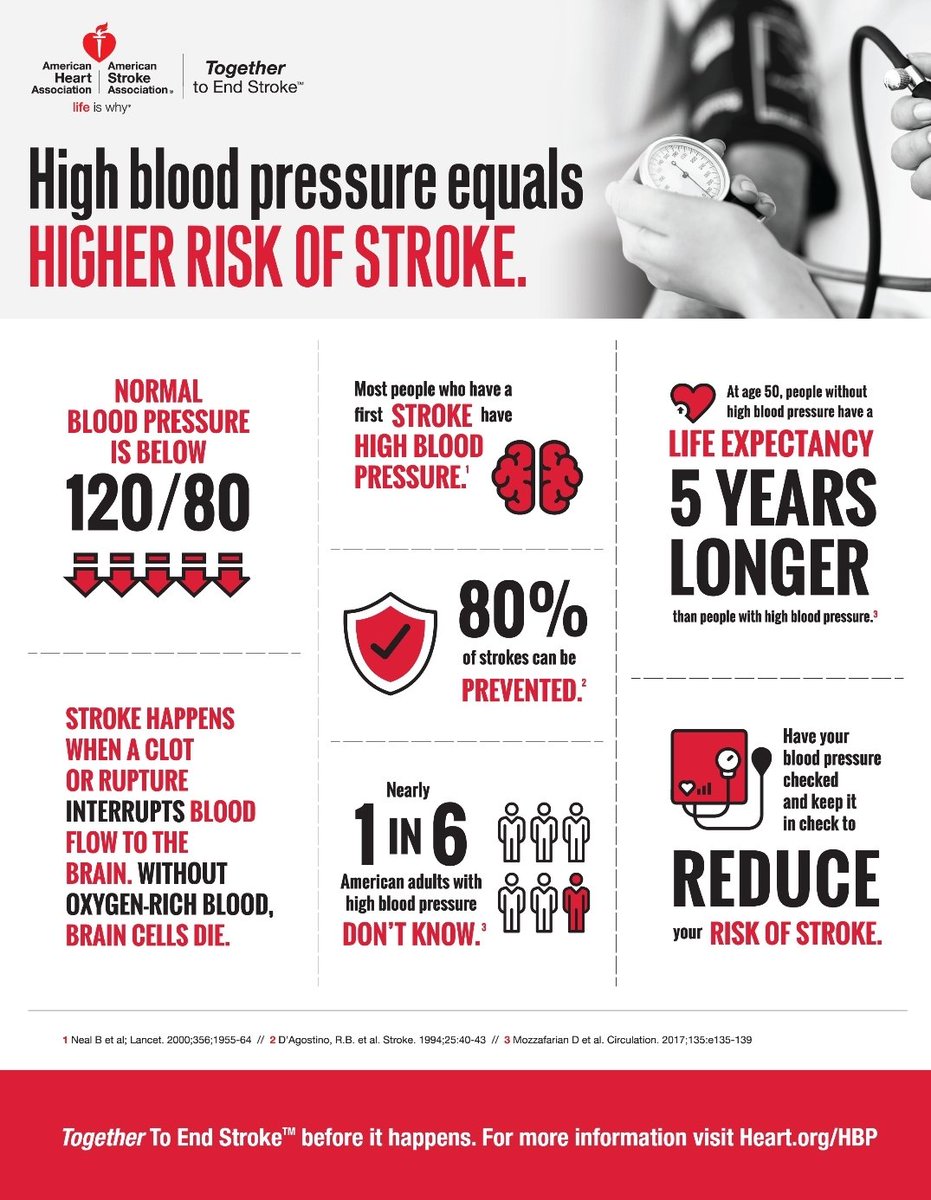

🧠ارتفاع ضغط الدم بشكل مفاجئ

🧠ارتفاع ضغط الدم بشكل مفاجئ

💥السيطرة ع #ضغط_الدم

💥السيطرة ع #ضغط_الدم

🧠ارتفاع الضغط

🧠ارتفاع الضغط

💥لذلك تذكر

الوقت هو الاهم في علاج السكته الدماغيه

💥لذلك تذكر

الوقت هو الاهم في علاج السكته الدماغيه